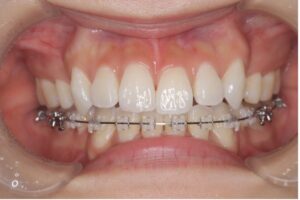

ワイヤー矯正は歯の表側や裏側にブラケットという装置をつけ、ワイヤーを通して歯を動かす方法です。

幅広い症例に対応できるのですが、ワイヤー矯正の中にも種類があるので紹介していきます。

一般的によく見られる矯正装置で、他のワイヤー装置に比べると比較的費用が抑えられます。

装置が舌に触れないため発音への悪影響や舌の痛みが起こりにくいところが利点ですが、唇の内側に装置が当たるため慣れるまで口内炎ができやすいのが欠点です。装置が当たるところには専用のワックスで装置を覆うことで、当たるときの痛みを和らげることができます。